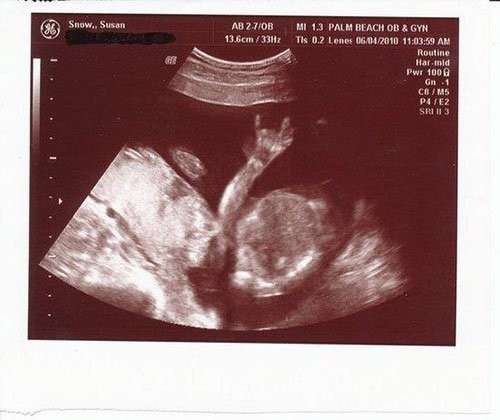

Bebek ve kediler